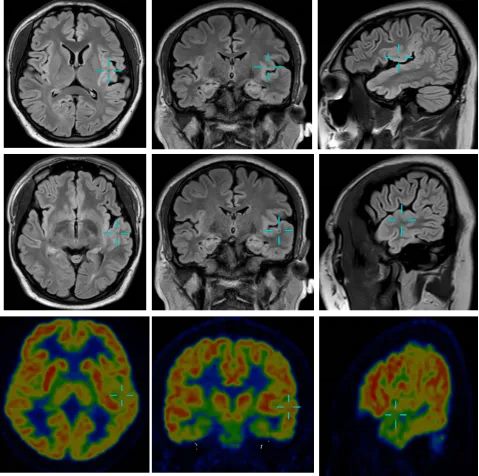

患者为25岁男性,患有药物难治性癫痫长达7年。接诊医师李信晓博士通过仔细询问病情,发现患者近3岁开始学说话,语言发育明显迟缓。术前影像学检查提示其左侧额叶、岛叶及颞叶存在皮质发育不良,但致病灶与语言、记忆等重要功能脑区的关系尚不明确,直接手术风险较高。经神经内科、神经外科、神经心理、神经电生理及影像科专家共同讨论,一致决定采用Wada试验“绘制”该患者的大脑功能地图。

手术在神经外科二病区李培栋主任医师指导下,陈超博士精准穿刺患者股动脉,将微导管超选插入目标颈内动脉,注入小剂量短效麻醉药物,使一侧大脑半球功能暂时抑制。在药物起效期间,团队对患者进行了标准化的语言、命名、记忆等项目测试,同步脑电图监测显示对侧肢体活动出现短暂暂停。

根据神经电生理科吴艳芝副主任医师的脑电图及测试结果,患者癫痫病灶所在半球仍为功能优势半球。在不影响患者语言与记忆功能的前提下,团队计划进一步实施立体定向脑电图(SEEG)电极植入,为患者制定个性化手术方案。